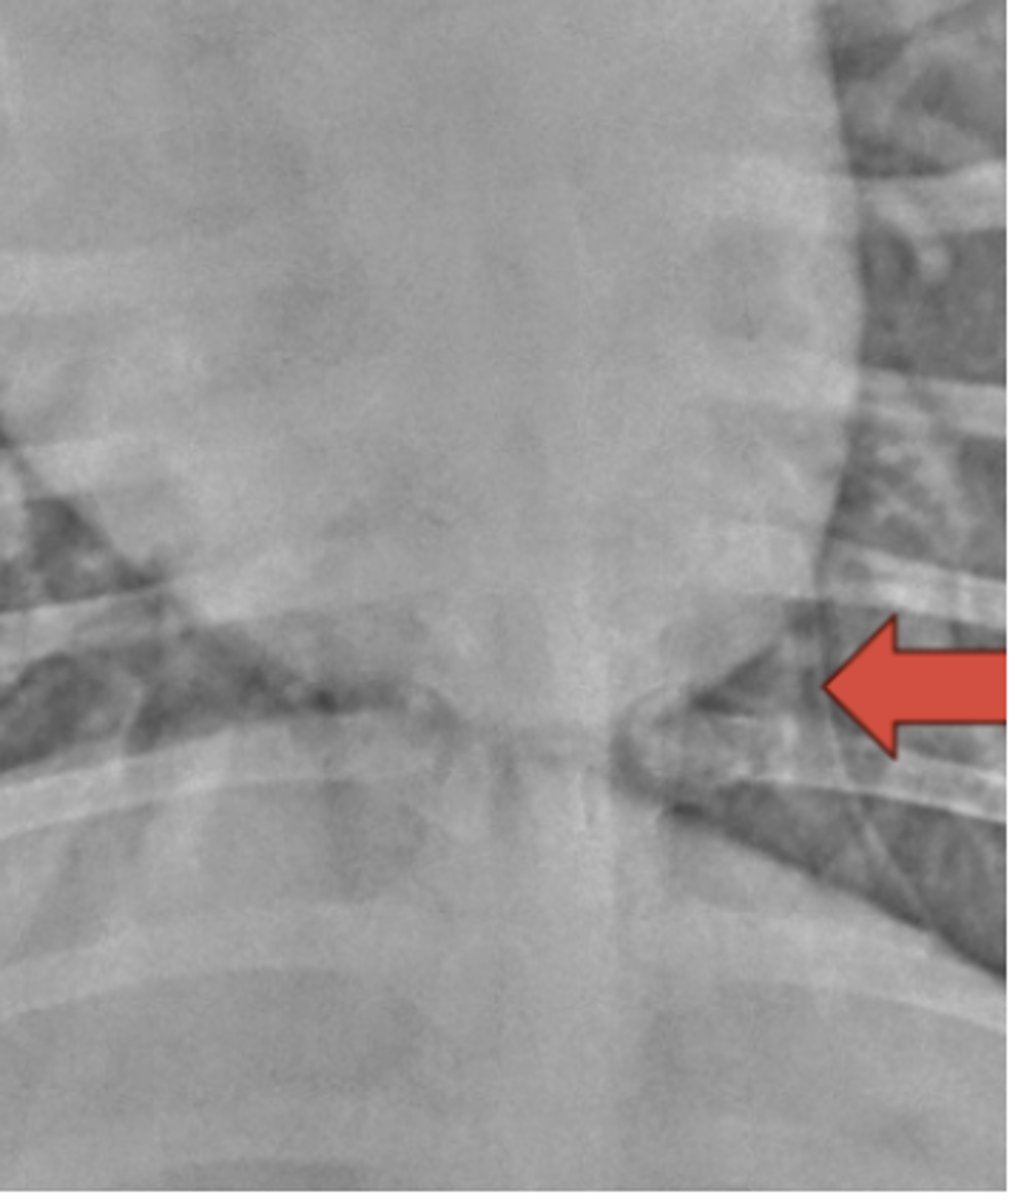

Mediastinal reflection

What structure is indicated by the arrow?